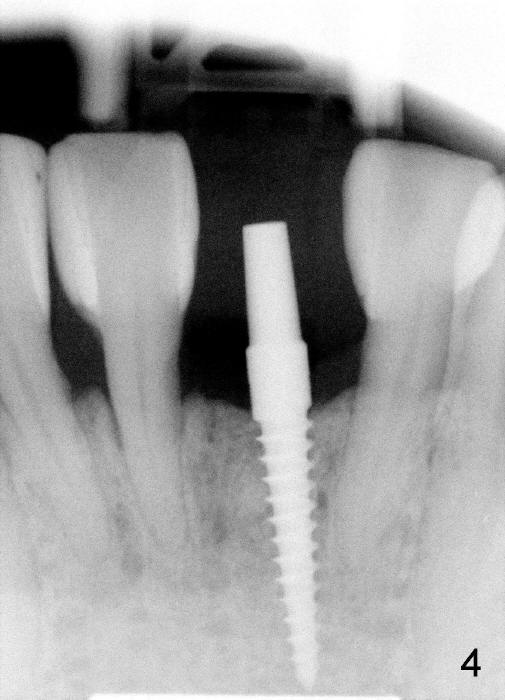

A 3x17 mm one piece implant is planned. Osteotomy is created by a 1.5 mm pilot drill at the depth of 14 mm without incision (Fig.2); it is close to a neighboring incisor. The trajectory of the osteotomy is intended to be changed (Fig.3 red) without success (white, 17 mm deep). With measurement and calculation, the 3x17 mm implant is not expected to touch the root of the adjoining tooth. In fact it is fine with insertion torque between 50-60 Ncm (Fig.4). Without incision, the papillae appear to form immediately following implantation (Fig.5). With adjustment of the abutment (Fig.6), an immediate provisional is fabricated (Fig.7).

To place the implant correctly, the preop PA should be studied carefully to find the divergence of the roots of the neighboring teeth (Fig.1). The depth of the initial osteotomy should be shorter, for example, 11 mm instead of 14 mm. Once the trajectory is found to be corrected, an incision should be made; the osteotomy is to be overcorrected with Lindermann bur (Fig.8 black); the whole osteotomy is changed with proper angulation (Fig.9 arrows).

Fig.10,11 show 7 day follow up. The permanent crown is seated 4.5 months postop (Fig.12). Minimal bone resorption occurs at the crest 4 months postop (Fig.13), which is most likely associated with conservative approach (flapless). The patient returns for follow up 2.5 months post cementation (Fig.14,15). The implant remains in the bone 4 years post cementation (Fig.16 CT coronal section; lingual thread exposure, corresponding to preop defect in Fig.1). There is mild coronal bone resorption 5 years 4 months post cementation (Fig.17).